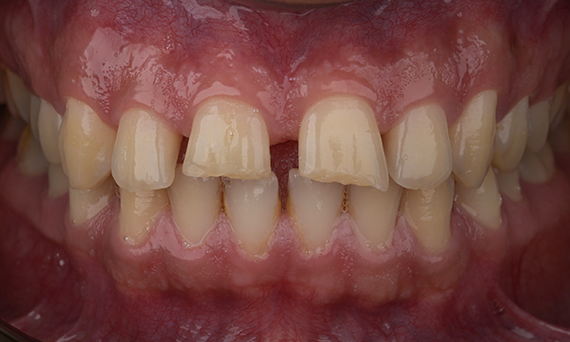

Amelogenesis Imperfecta

Full mouth rehabilitation with 28 all-ceramic restorations

A particular and protracted case of skeletal Class II malocclusion and generalized amelogenesis imperfecta in a teenager was referred for prosthetic rehabilitation. The aim of the treatment was to prepare the remaining tooth structure, remove undercuts, and make room for all-ceramic crowns covering the entire dentine and simulating the lost enamel.

Before: Initial situation prior to orthodontic treatment.

After: Final result, 1 week post-operative.

Alexander Declerck, (DDS, MSc)

Sint-Martens-Latem, Belgium